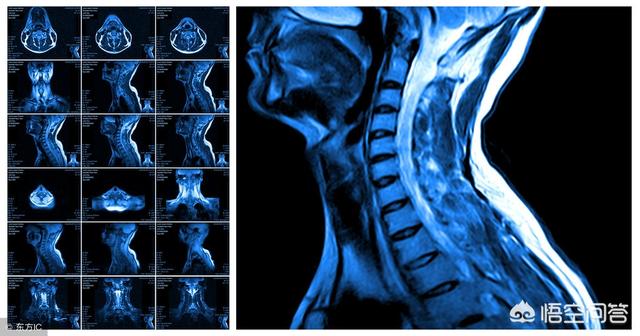

上述问题造成的手臂疼痛,还是很好解决可自行处理的,但是,假若根源不是肌肉,自己是很难分析和处理的,例如,颈椎间盘突出压迫神经根,颈丛神经卡压,臂丛神经在斜角肌卡压等,这要看医生。